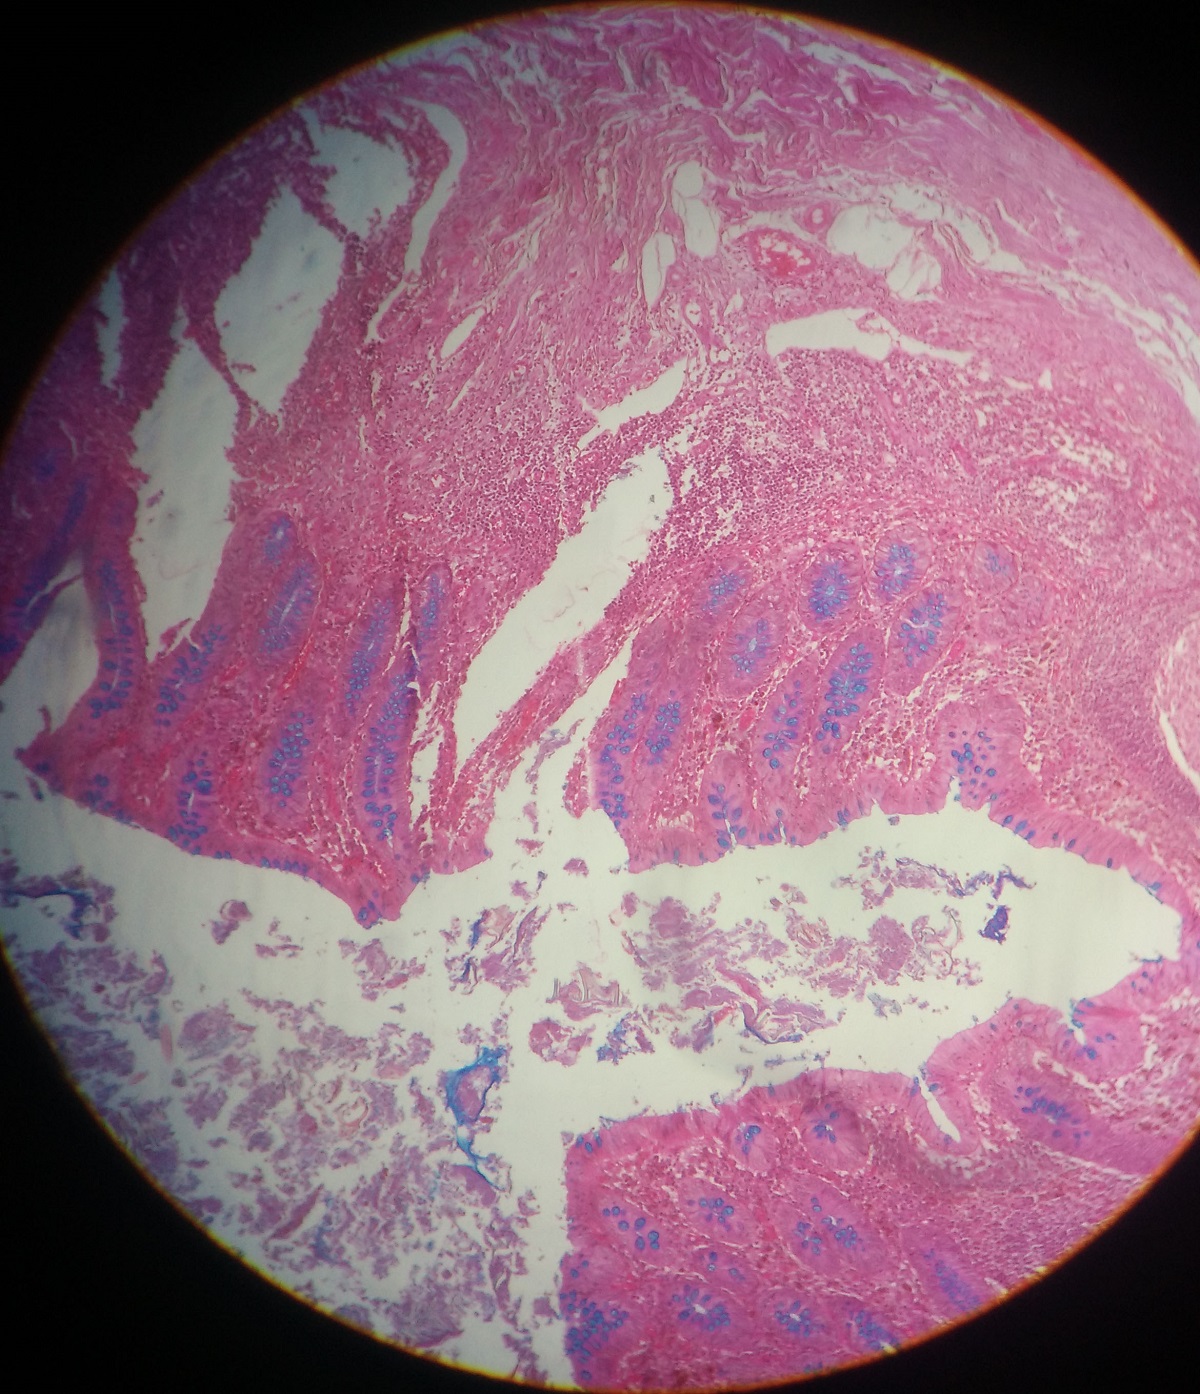

Appendix

Lymphoid masses within mucosa and submucosa often forming germinal center

Mucosal glands are much less closely packed than large intestine